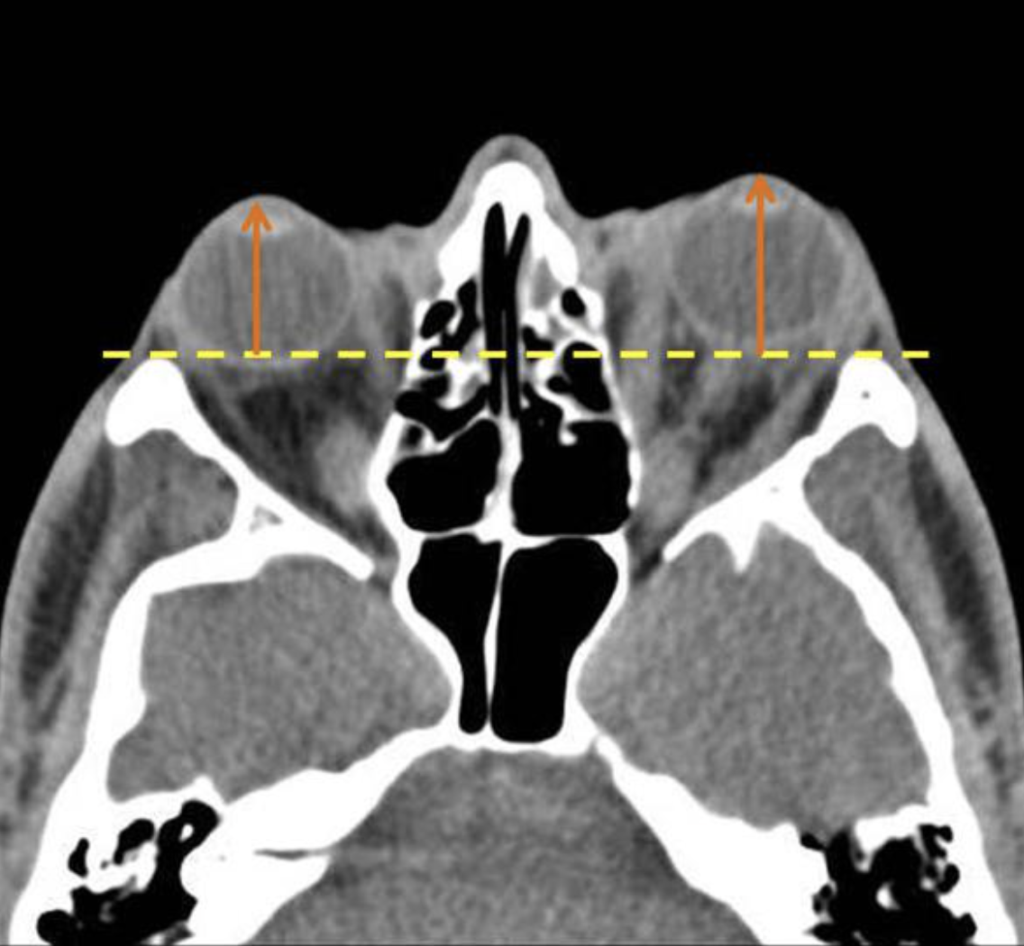

Appendix 1

Axial CT images and at a level of the lens. If the distance from the anterior margin of the globe to interzygomatic line exceeds 21 mm, it is compatible with proptosis. In the case above the distance from anterior margin of the globe to interzygomatic line is 23 mm (right) and 25 mm (left). The findings are compatible with ocular proptosis due to thyroid ophthalmopathy.